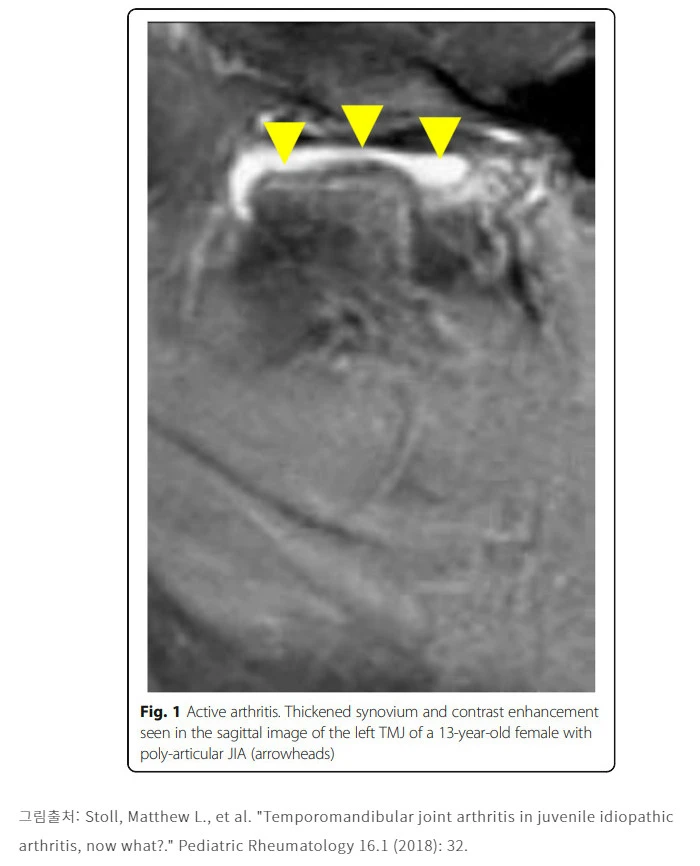

살다보면 염증도 발생을 하게 됩니다. 턱관절 염증은 생각보다 파괴적인 측면이 있어서 잠시 통증이 있고 붓고 음식먹을 때 불편한 수준으로 끝나기도 하지만 염증이 제대로 해결이 안되서 만성으로 진행된다거나, 아니면 처음부터 센 놈이 와서 턱관절 염증을 무지막지하게 유발하게 되면 문제가 됩니다. 후자의 경우 소아에서 특발성으로 발생하는 류마티스관절염이 턱관절에 이환된 형태가 보편적입니다.

이런 일이 발생하면 턱관절 디스크를 싸고 있던 활막이 염증이 생겨서 두꺼워지고 이 염증은 점차로 그 주위조직에 파급되어 심하면 하악과두에도 영향을 미치게 됩니다. 하악과두는 뼈죠? 그래서 뼈에 염증이 생기면 조직 리모델링이 일어나면서 뼈가 파괴가 되기도 하는데 이를 골침식이라 부르게 됩니다.